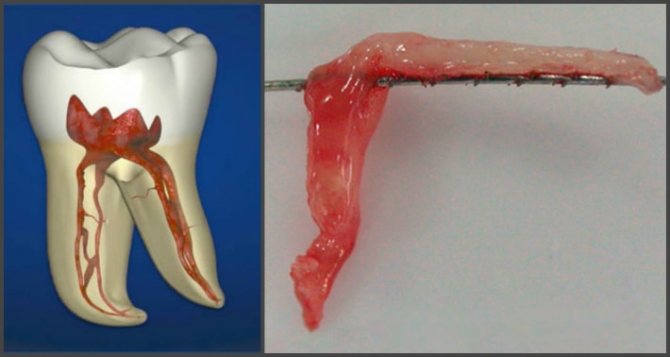

Зуб не является одним сплошным костным образованием, покрытым слоем эмали. Внутри он имеет полость, которая распространяется и в его корни, образуя длинные зубные каналы. Эта полость заполнена так называемой пульпой, выглядящей как рыхлая волокнистая ткань, в живом и здоровом состоянии имеющей насыщенно розовый цвет благодаря наличию большого количества капилляров.

Пульпа состоит из волокон соединительной ткани и множества клеток различного назначения, которые единой гомогенной массой окружают нервно-сосудистый пучок. Эти пучки проникают в зуб через отверстия в корнях и являются ответвлениями челюстных нервов и сосудов.

Благодаря артериолам зубные ткани получают кислород и питательные вещества, по венам удаляются продукты метаболизма и углекислый газ, а нервные проводники обеспечивают регуляцию всех этих процессов. Расположенное по периферии пульпы нервное сплетение, называемое сплетением Рашкова, отвечает за болевой синдром при пульпите.

- Частичное или полное удаление пульпы.

- удаление пульпы зуба (проводится при помощи специального инструмента),